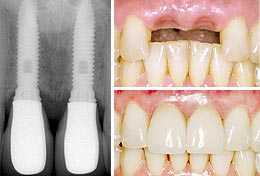

The process of osseointegration is what allows your dental implant to become integrated with your jaw bone, making it a natural part of your mouth. The term comes from the Latin osseo, meaning “bone” and integrate, meaning “to make whole.”

This process can only occur in the human body with certain materials, which is why titanium is the most commonly used material for dental implants. In the 1950s, it was discovered that bone could grow around and bond to titanium, and this discovery was partially responsible for the invention of dental implants.

Once your dental implant is placed, the process of osseointegration begins. Over time, the bone surrounding your implant will continue to grow around it and bond to it, locking it into place and preventing it from moving or shifting.

This process can take anywhere between 3-6 months. While you may feel as if your mouth has completely healed from its dental implant within just 2 weeks, osseointegration may take 3-6 months or longer, depending on the health of your jaw bone and your overall health. This is why the process of placing a dental implant at Southington Dentistry takes longer than other alternative restorative therapies.